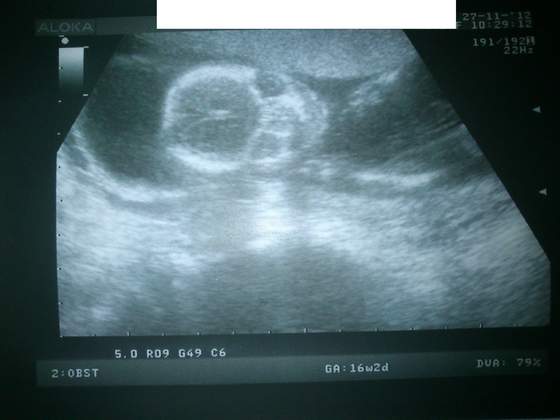

biedroneczka1980 a jak ładnie mózg widać

Mam takie zdjęcie Kuby i osobiście uważam, że wygląda, jak mucha:-)

Biedroneczka, jaki cudny alien! Małe dzieci naprawdę wyglądają jak kosmici i nie widzę w tym twierdzeniu nic zdrożnego. W końcu jako ludzie jesteśmy też na początku przez jakiś czas płazami...

biedroneczka - piękne zdjęcie, gratulejszyn!